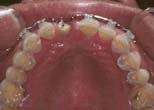

Forced eruption